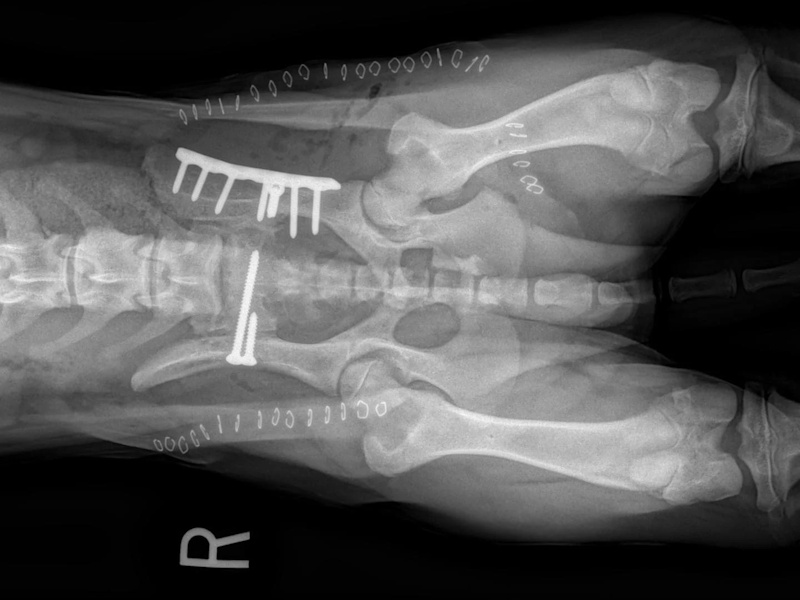

An osteotomy is a surgical cut in a bone. In the cruciate deficient stifle, a cut is made in the top of the tibia. The top portion of bone that contains the articular surface is rotated to level it. The two pieces of bone are held in place with a metal plate and screws.

Post Surgical Radiographs

While the patient is still anesthetized, the patient is taken into radiology for post-surgery radiographs (X-rays). The radiographs are assessed to measure the new tibial plateau angle. We are aiming for 5-6 degrees relative to the long axis of the tibia. The apparatus (plate and screws) are assessed for size and appropriate position.